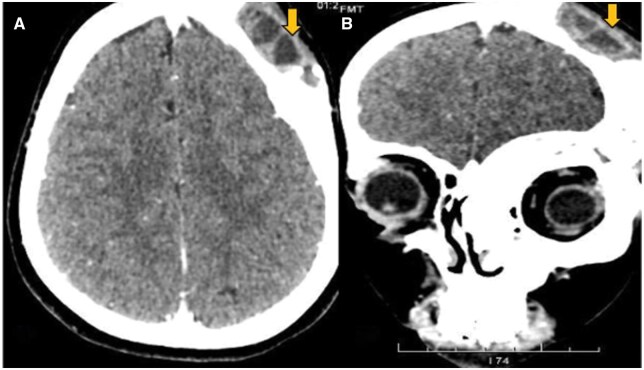

Fibrous dysplasia (FD) is a benign condition affecting osteoblasts, which fail to undergo proper differentiation and maturation, resulting in the replacement of normal osteoid matrix with ground glass fibrous tissue. Aneurysmal bone cyst (ABC) is a benign, expansile, lytic lesion characterized by multiple blood-filled cystic cavities containing haemorrhagic products at varying stages. Secondary ABC arising from craniofacial FD is extremely rare. To date, only 10 cases have been reported in the literature. This report highlights the clinical presentation, imaging findings, and histopathological confirmation of a secondary ABC in a patient with polyostotic craniofacial FD.